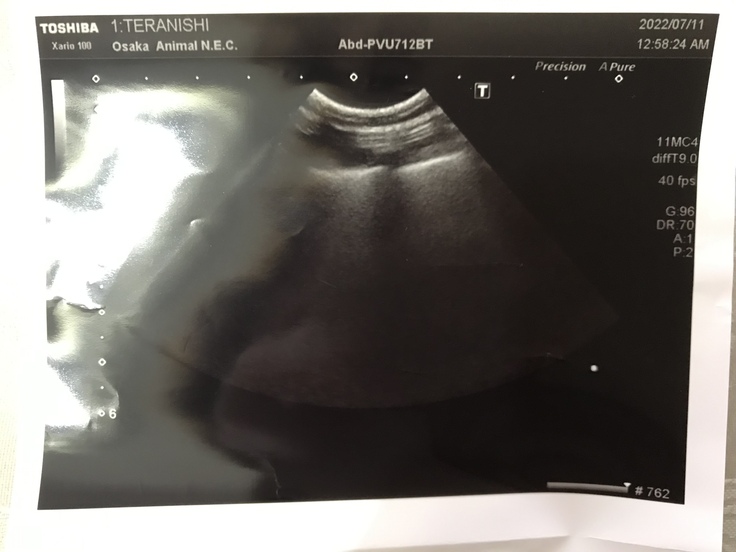

そして、心臓血管外科の病院で血液検査と心臓の超音波検査をして、弁の状態と腎臓の状態を診てもらいます。手術日まで内科と外科を併診していきます。